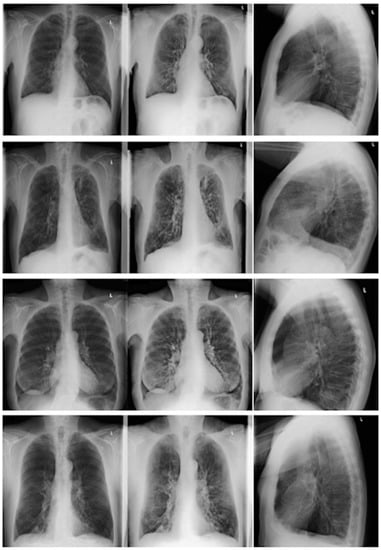

2. Materials and Methods

2.2. Data Acquisition

2.2.1. CR and DE Images

2.3.1. CR/DE Image Analysis

3.5. CR and DE Image Analysis

3.5.3. Severity of Emphysema between CR/DE and CT